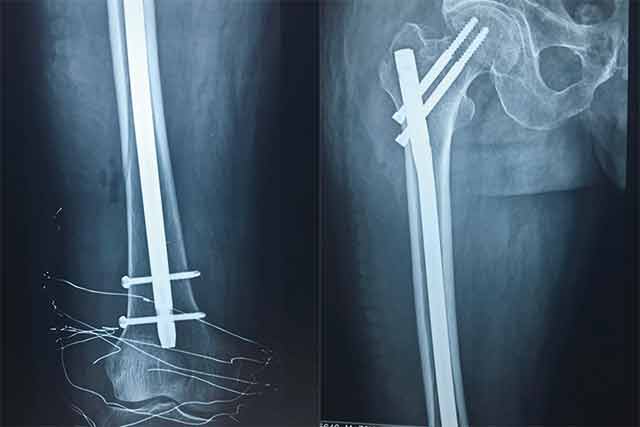

▲術(shù)后

經(jīng)過骨科專家團(tuán)隊(duì)的詳細(xì)查體以及相關(guān)拍片、CT等輔助檢查,韓大爺被診斷為右側(cè)的股骨干骨折合并同側(cè)粗隆間骨折。通過和病人及家屬耐心細(xì)致地溝通,韓大爺收住我院骨科。經(jīng)過詢問病史,了解到韓大爺有胃出血及疝修補(bǔ)手術(shù)史約10余年,并伴有老年高血壓病史,年事已高、病情復(fù)雜,需要制定更為詳細(xì)的診療方案。骨科主任楊連海及副主任孫守全立即組織科內(nèi)討論,充分與患者家屬進(jìn)行溝通、以得到家屬的認(rèn)可,細(xì)致而縝密地結(jié)合病人的個(gè)體情況定制手術(shù)方案。由于病情復(fù)雜,麻醉科主任修冬云在手術(shù)前親自看望韓大爺?shù)纳眢w狀況,認(rèn)真分析評估手術(shù)的風(fēng)險(xiǎn)程度,排除手術(shù)禁忌,選擇合適的麻醉方式。經(jīng)過積極的術(shù)前準(zhǔn)備,孫守全副主任擇期在硬膜外麻醉下完成了髖部骨折+同側(cè)股骨干骨折髓內(nèi)重建釘?shù)膬?nèi)固定手術(shù),手術(shù)過程非常順利,骨折復(fù)位基本達(dá)到解剖復(fù)位。術(shù)后經(jīng)過預(yù)防感染、鎮(zhèn)痛、預(yù)防下肢深靜脈血栓等治療,韓大爺恢復(fù)的非常好,沒有出現(xiàn)感染、血栓等并發(fā)癥,而且傷口甲級愈合。